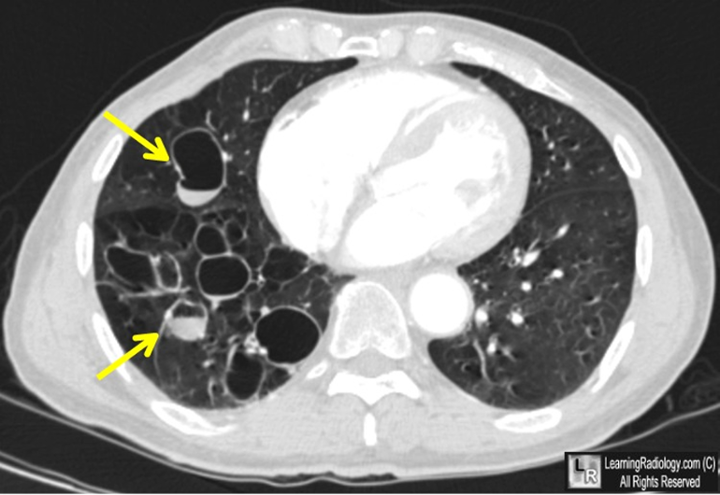

Bệnh giãn phế quản được chẩn đoán bằng hình ảnh X-quang phổi và CT ngực. Tuy nhiên chụp CT ngực lớp mỏng độ phân giải cao có giá trị nhất trong chẩn đoán xác định.

Chụp CT giúp xác định vùng và mức độ nặng của bệnh giãn phế quản và có thể xác định một số nguyên nhân gây bệnh.

CT ngực bệnh nhân GPQ, các nhánh PQ giãn to và ứ mủ bên trong (mũi tên)